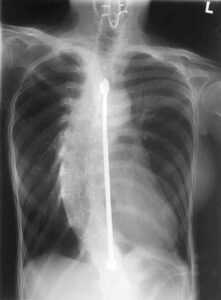

Presso l’Ospedale Ulss n.4 "Alto Vicentino” di Schio, centro d’eccellenza nella chirurgia vertebrale per il Nord Italia, il Prof. Massimo...